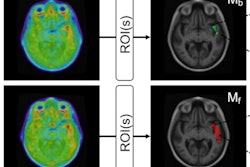

Associations of baseline beta-amyloid PET and baseline phosphorylated tau-181 (p-tau181) with F-18 flortaucipir (FTP) Standardized uptake value ratio (SUVR) annualized change for (A) cognitively unimpaired and (B) cognitively impaired individuals. Brain surface renderings depict Pearson correlation coefficients adjusted for age and sex (r) representing the strength of the association between the different biomarkers and F-18 flortaucipir SUVR change in each brain region. The right upper panel represents age- and sex-adjusted Pearson correlation coefficients (r), along with p-values, for the association between the biomarkers and F-18 flortaucipir SUVR change in the Alzheimer's disease meta-region of interest (ROI). The root mean squared error (RMSE) for the prediction of F-18 flortaucipir SUVR change by a linear model with the biomarker as predictor and age and sex as covariates. RMSE was estimated using leave-one-out cross-validation. Voxel-wise statistical maps were thresholded using more lenient cluster-forming thresholds of p < 0.05 (uncorrected) at the voxel level and further thresholded at the cluster level by restricting results to clusters with a number of voxels higher than the expected number of voxels as predicted using random field theory. Image courtesy of Alzheimer's & Dementia: The Journal of the Alzheimer's Association.